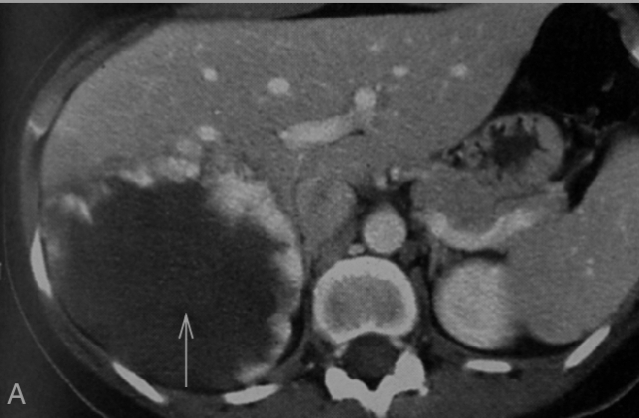

Hémangiome caverneux du foie : TDM hépatique avec injection de contraste.

Publié par : Kamal nadifi